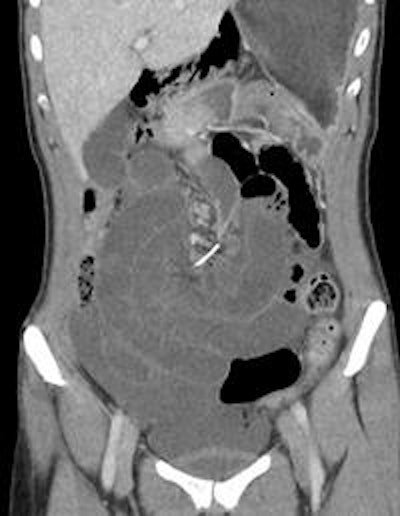

The patient underwent a CT scan of the abdomen, and a metallic, wire-shaped foreign body was found. The wire had pierced several parts of the small bowel, causing a small-bowel volvulus, or obstruction.

The patient underwent emergency surgery. The surgeons discovered a 7-cm-long piece of orthodontic wire had caused ischemia, or restriction of blood supply, of the mid-small bowel. The wire had penetrated through the small bowel and small-bowel mesentery to another loop of the mid-small bowel.